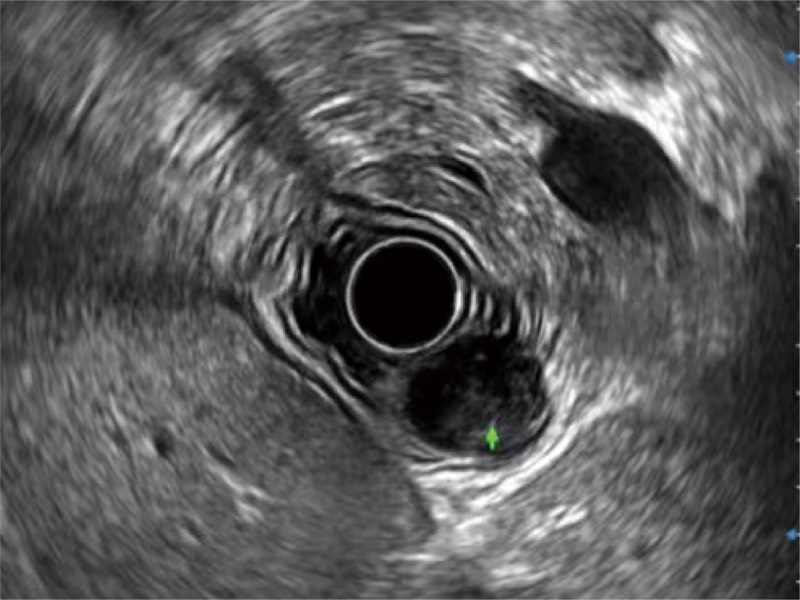

• 食管内间质瘤清晰显像

• 360°电子环形扫查与高清内镜影像相结合,提供了良好的插入性能和高清的内镜图像

卓越的宽频设计,满足医生探查不同深度的组织和器官